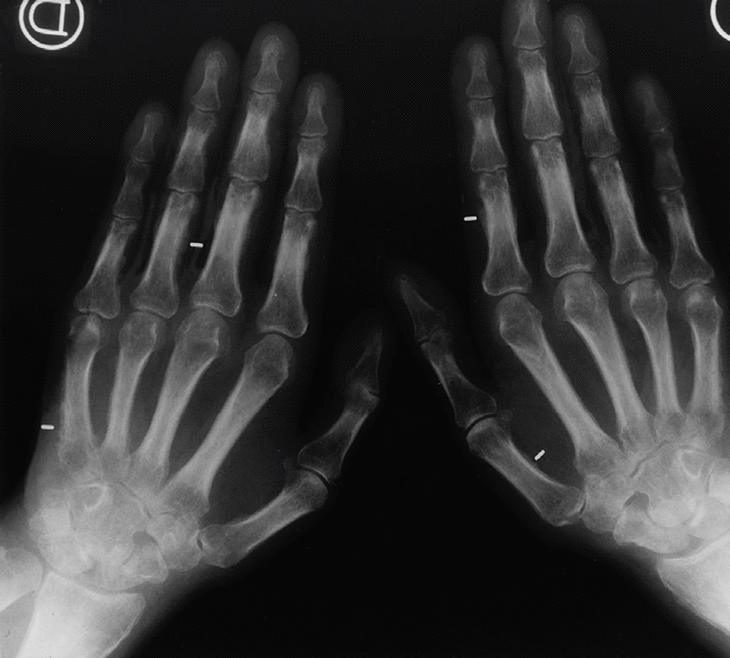

Presentamos el caso de un varón de 60 años que aporta radiografía de tórax con nódulo pulmonar cavitado y signos de bronconeumopatía crónica obstructiva (BNCO) (fig. 1). Se le realiza fibrobroncoscopia diagnosticándose carcinoma epidermoide.

Fig. 1

El paciente acusa además dolor en manos y piernas, por lo que se le realizan radiografías anteroposteriores de dichas regiones donde se observa intensa reacción perióstica ondulante en tibias, peronés, metacarpianos y falanges, compatible con osteoartropatía hipertrófica pneúmica (OAH) (figs. 2 y 3).